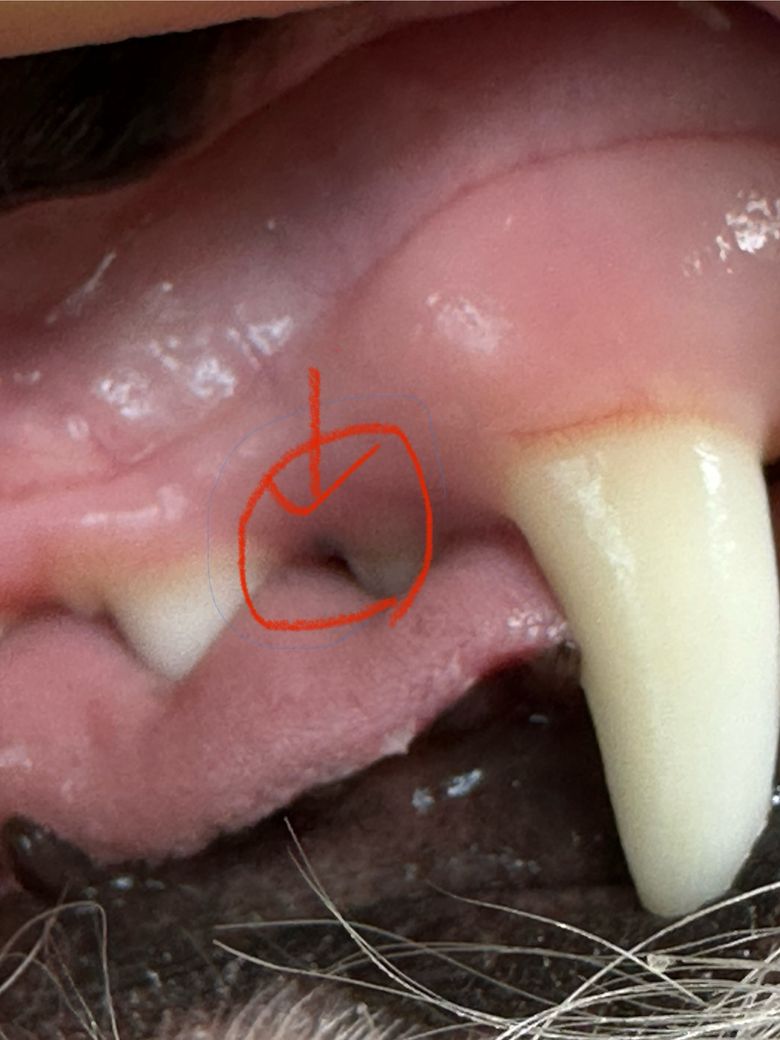

강아지 잇몸에 청색?검푸른색 아주작은 점?이 생겼어요. 처음에는 저거보다 엄청 미세햇는데 점점 커지는 거 같아요…저게 뭘까요??

• 점의 크기가 점차 커지고 있다면 단순한 색소 침착보다는 구강 흑색종이나 기타 종양성 병변일 가능성을 염두에 두고 즉시 수의사의 진단을 받아야 합니다. 보통 강아지 잇몸의 검은 점은 멜라닌 색소 증가로 인한 렌티고 즉 흑자일 가능성이 높고 이는 건강에 무해하지만 시간이 지나면서 크기가 커지거나 형태가 변하는 것은 단순 색소 침착과 구분되는 임상적 징후입니다. 2살이라는 나이를 고려할 때 악성 종양의 확률은 통계적으로 낮으나 육안만으로는 양성과 악성을 명확히 구분할 수 없으므로 병원에서 세포 검사나 조직 검사를 진행하여 정확한 병명을 확인하는 것이 논리적인 대응입니다.